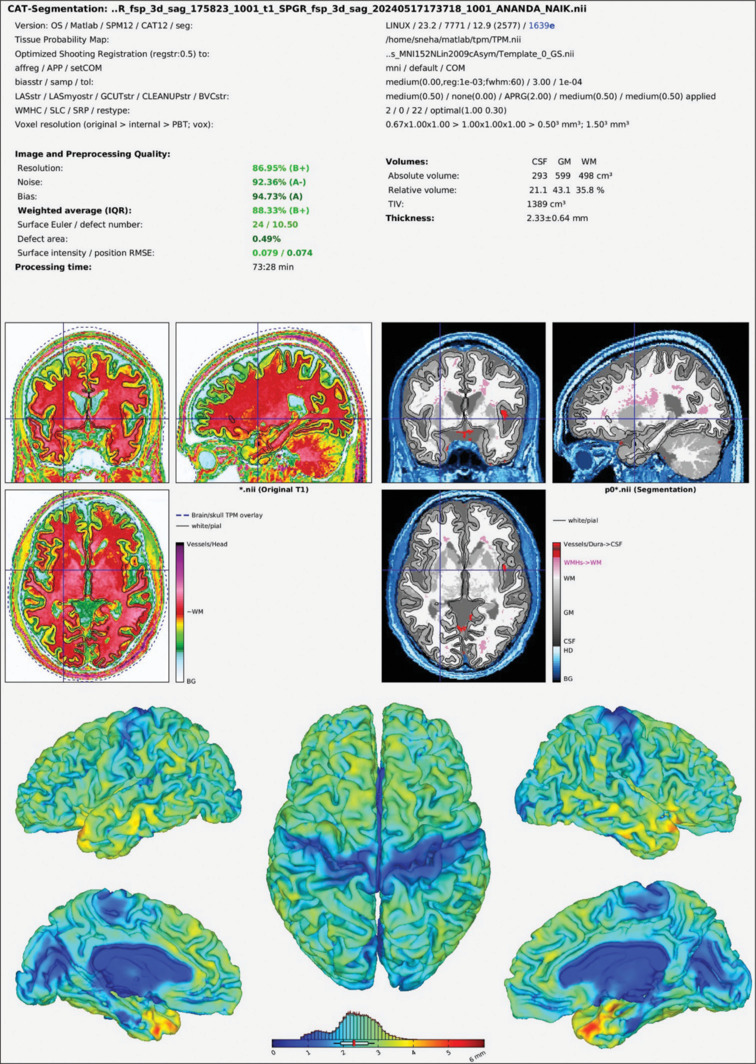

Materials and methods: The study involved 90 individuals aged between 18 and 35 years, who were categorized into three groups: control (n = 30), obese (n = 30), and hypertensive (n = 30). The researchers used magnetic resonance imaging (MRI) scans to examine the brain's structure, specifically analyzing the volume of different regions. The researchers assessed cognitive function using the flanker task to measure selective attention and the n-back task to evaluate working memory. Statistical analysis involved the use of one-way analysis of variance (ANOVA) and Games-Howell post-hoc tests.